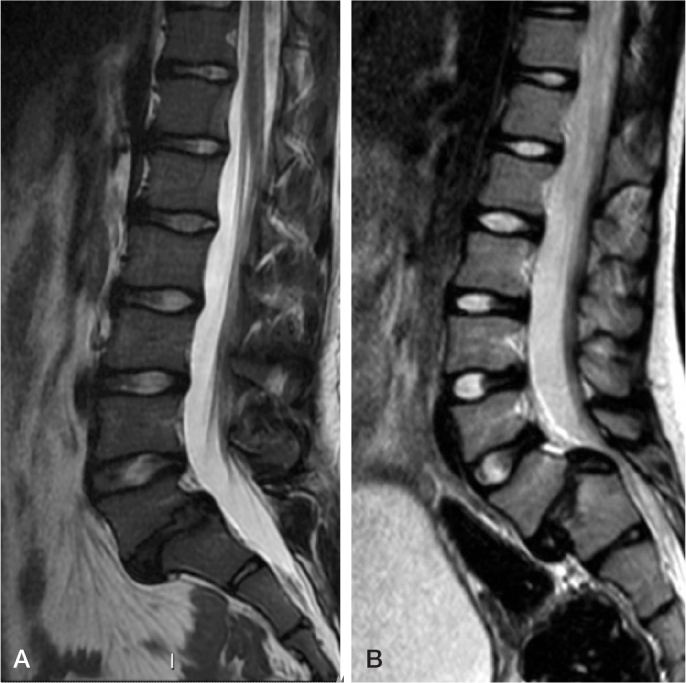

峡部裂被定义为腰椎关节间部缺损或伸长,单侧或双侧均可。患有双侧峡部裂的成长期儿童可能会出现椎体滑脱,即受影响的椎体向前滑动。峡部裂的病因被认为是由于与遗传易感性相关的重复性负荷导致的应力性骨折。腰椎磁共振成像(MRI)显示在实际骨折线形成之前信号强度增加。在轻度椎体滑脱中,三分之二的急性小儿椎体滑脱患儿会在早期活动受限的情况下进行骨愈合。与骨不愈合的患者相比,实现骨愈合的患者的健康相关生活质量得到改善,其中四分之一的患者会进一步发生脊柱滑脱。对于高度椎体滑脱的患者(定义为受影响椎体向前滑动超过50%),建议进行脊柱融合术以防止进一步进展。

Spondylolysis is defined as a defect or elongation in the pars interarticularis of the lumbar spine, either unilateral or bilateral. Growing children with bilateral spondylolysis may develop spondylolisthesis, i.e., forward slipping of the affected vertebra. The etiology of spondylolysis is regarded as a stress fracture due to repetitive loading associated with a genetic predisposition. Lumbar magnetic resonance imaging (MRI) shows an increased signal intensity before an actual fracture line develops. In low grade spondylolisthesis, two-thirds of children with acute pediatric spondylolysis will undergo bony union with early activity restriction. Health-related quality of life is improved in patients achieving bony union as compared with patients having non-union, of which one-fourth will additionally develop spondylolisthesis. In patients with high-grade spondylolisthesis, defined as a more than 50% forward slippage of the affected vertebra, spinal fusion is recommended to prevent further progression.